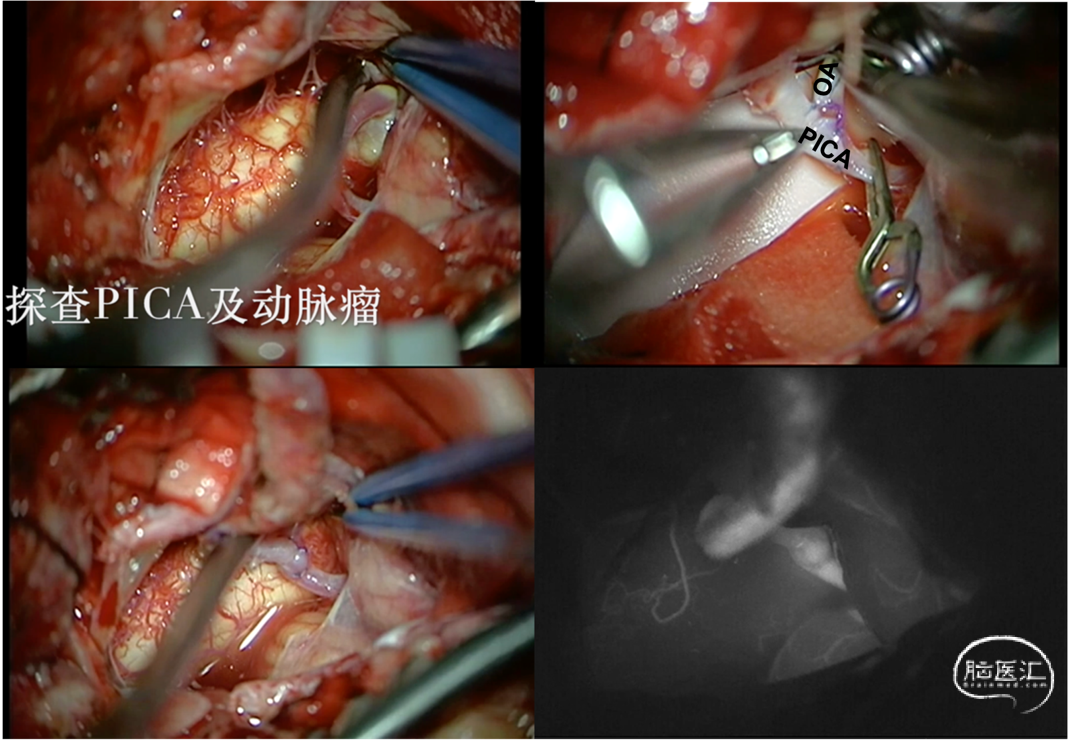

2.探查载瘤动脉PICA及动脉瘤瘤体,选取PICA P3段行OA-PICA端侧吻合,重建PICA血运(图5)。

图5.术中抬起小脑扁桃体探查患侧PICA及动脉瘤流入道和流出道,选取延髓背侧段(P3段)PICA行OA-PICA端侧吻合,术中ICG提示重建血管通畅。